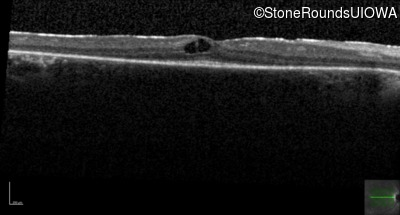

Optical Coherence Tomography - Right -

20/20 -1

Exemplar / OCT Stack